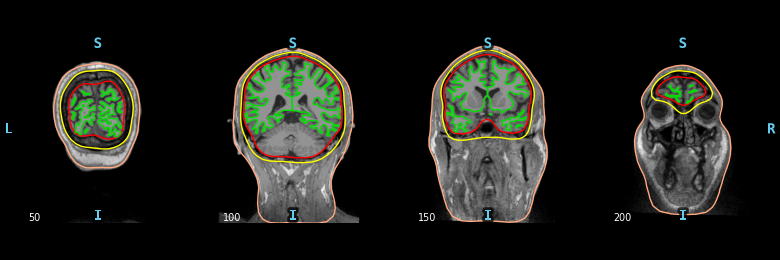

It produces outputs like this: The slicing order and labeling of each axis has already been done in there somewhere. Following the trail: And to see how data should be manipulated to plot properly, you want to look in Line 391 in 474da96 Ideally you could just use |

The BEM code 1) resolves orientations so that they can be plotted sagittal/axial/coronal, 2) shows the slice number, 3) displays L/R/A/P/I/S to the sides, 4) has contours-from-surfaces built in, 5) has been unit-tested and user-tested to make sure that non-standard orientations are shown properly. These all seem like useful features for the GUI, no? |

Sorry I got lost with the bounding box discussion but looking at the image it seemed to me that there was some affine registration issue but I might be wrong. I have seen those kinds of images when you do some registration and the corners become black because there are no pixels to copy from. It might be worth taking inspiration from MMVT. Maybe you were also a contributor @alexrockhill ? ;-) I like how in the sliced view the CT appears in a different color and makes it really easy to spot things. But I don't know if it's a standard way to do this ... |

This is how it was previously in EDIT: for MMVT, Noam was looking mostly at DBS which is usually well-spaced so there aren't bridged contacts and they come out super clean in the thresholded, blue version but with the SEEG CT data I have been working with, the bridged contacts make it so that you really need the background and no thresholding to get the full picture of the contacts. From the experience of actually having done this process for an experiment, I can tell you that the method currently on this branch works better even if it isn't as aesthetically pleasing. Looking more closely, the black rectangle immediately surrounding the skull and the gray rectangle surrounding that are actually part of the underlying image. I really would prefer not to mess with this and the background because you wouldn't want to obscure something that might help you understand what's going on in the CT and it's bounding. The outermost black background is what happens when you zoom out of a matplotlib image so that one could be fixed but again I would strongly prefer to leave it as is. |

Add a GUI that allows users to find their intracranial electrode montage from a CT, an MRI and the Freesurfer recon-all from it, and an

infoobject that supplies the names to be found and is return with a modified montage.Closes #9559